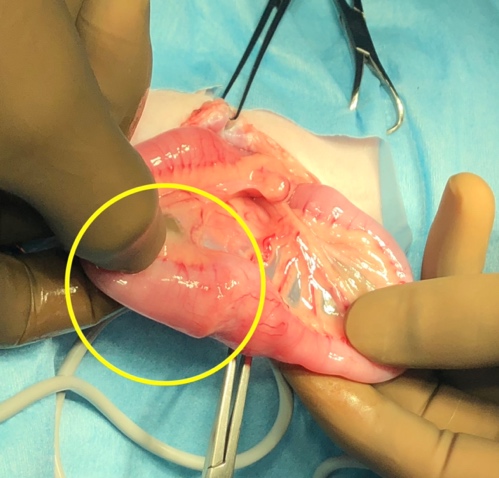

腸管の腫瘍

症状は多様であるが、嘔吐や食欲不振、腹痛などを示します。

腸の閉塞や腸の穿孔を示すと急性の症状を示すこともあります。

犬では腺癌や胃腸間質腫瘍(G I S T)平滑筋肉腫など、猫ではリンパ腫が他の腫瘍よりも多い。腸の切除と吻合術により、腫瘍の両側にマージンをつけて広範囲の切除を行います。